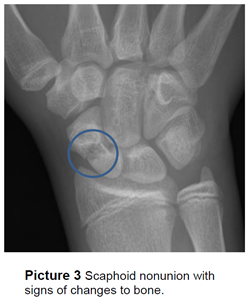

A scaphoid fracture nonunion is when the

bone pieces fail to heal together. Typically

this occurs because of a missed or delayed

diagnosis.

A nonunion can also lead to avascular necrosis (AVN), when a lack of blood supply to a bone causes it to die. AVN can lead to early arthritis in the wrist. Blood flow to the scaphoid bone occurs via retrograde (‘backwards’) flow, meaning blood enters at the distal (top) portion of the bone and there is no direct blood supply to the proximal (bottom) portion of the bone. This retrograde blood supply is what can cause a fracture nonunion to go on to AVN (Picture 4).